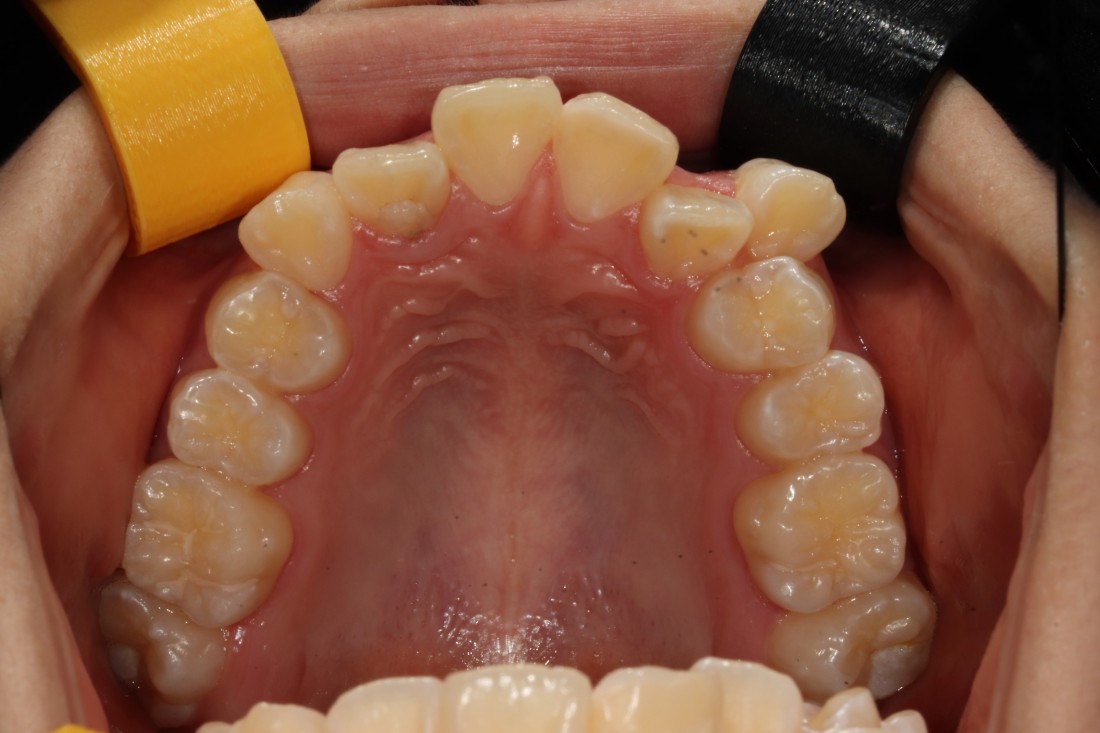

수완동 치아교정 기간은

치아의 이동속도에 따라

예상기간보다 짧아질 수도,

혹은 길어질 수도 있는데요.

월 3만원~5만원 사이의

월 진료비용이 발생하게 되면

몇 개월만 기간이 길어져도

수 십만원의 비용부담으로 다가오기 때문에

수완동 교정치과에서는

월 진료비를 포함하여

추가 금액 결제 없이

합리적인 가격으로

수완동 치아교정을 진행하고 있습니다.